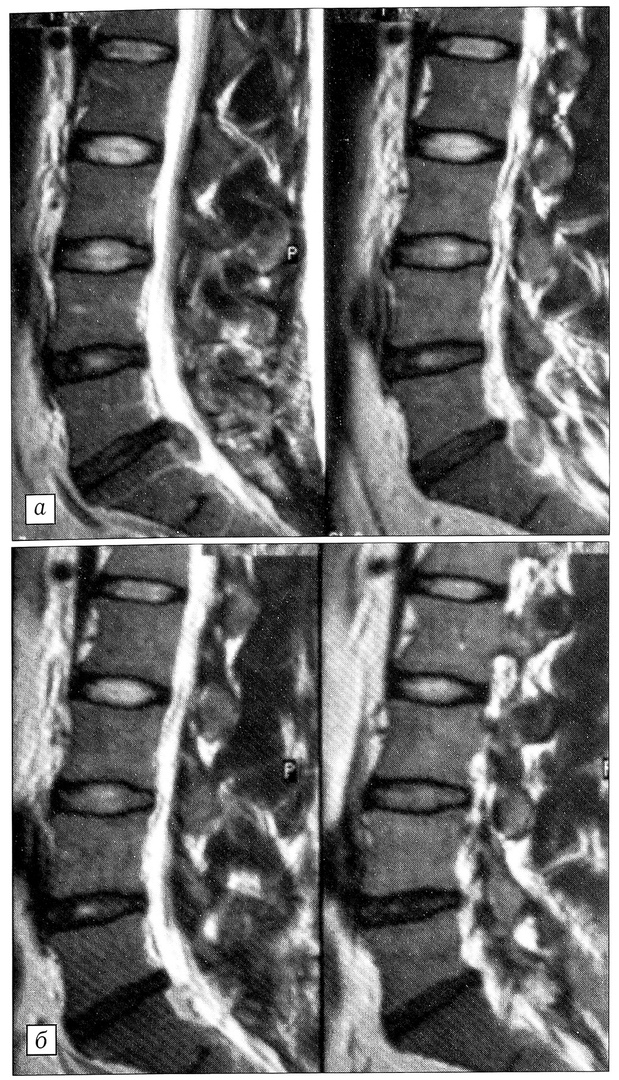

Рис. 3. МРТ поясничного отдела позвоночника больной К. в сагиттальной проекции: a — до операции, б — после операции.

Больная К., 60 лет, свыше 10 лет отмечает боли в поясничном отделе позвоночника, в последний год присоединились боли в левой нижней конечности. В поликлинике после обследования (рентгенография, МРТ) поставлен диагноз: дискоз L2-3, L3-4, L4-5; левосторонняя срединнобоковая протрузия диска L4-5; левосторонний компрессионно-корешковый (L5) синдром (рис. 3, а). Консервативное лечение в амбулаторных условиях в течение 2 нед оказалось неэффективным. Больная госпитализирована в хирургическое отделение 01.03.99, пройдя весь курс обследования амбулаторно.

02.03.99 под местной анестезией произведена чрескожная лазерная декомпрессия диска L4-5. Вечером того же дня больной разрешено ходить в ортопедическом поясе, начато восстановительное лечение. Выписана 05.03.99 со значительным уменьшением болевого синдрома (по карте болевого аудита — с 53 до 24 баллов). Через 3 нед приступила к работе. В течение года после операции повторных приступов боли в спине и нижних конечностях не возникало, на контрольной МРТ отмечается частичная редукция протрузии диска (рис. 3, б).